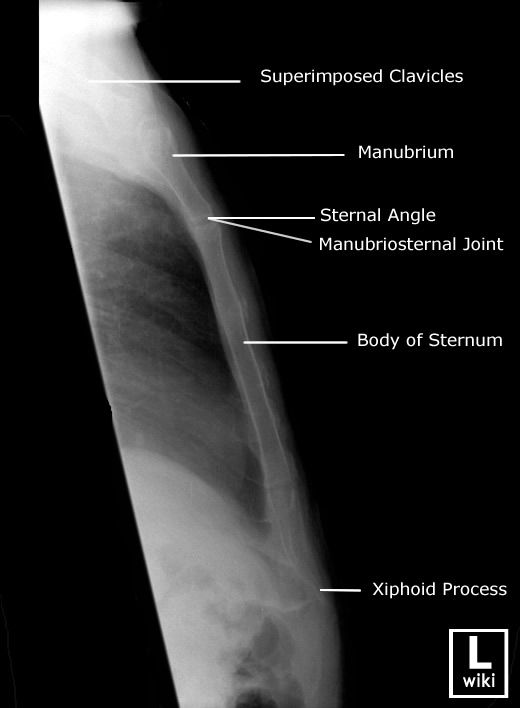

Explain patient and CR positioning for a lateral sternum

patient

erect

lateral position (R or L)

seated or standing

shoulders and arms drawn backward

recumbent

lateral position (R or L)

true lateral

arms raised above head, shoulders back

CR

perpendicular to mid-sternum entering lateral border

top of IR 1½ inches above jugular notch

What are breathing instructions for a lateral sternum? Why?

full inspiration; to get high contrast between posterior surface of sternum and lungs

What is SID for lateral sternum images?

Erect: 72”

Recumbent: 40”

Trauma shoot-thru: 40-72”

What needs to be demonstrated on a lateral sternum image (film eval)?

lateral view of entire sternum

any fractures or inflammatory processes

marker placed anterior for side down (usually L)

collimation anterior to posterior

oriented how you took the image